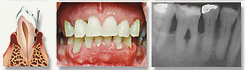

moderate periodontitis